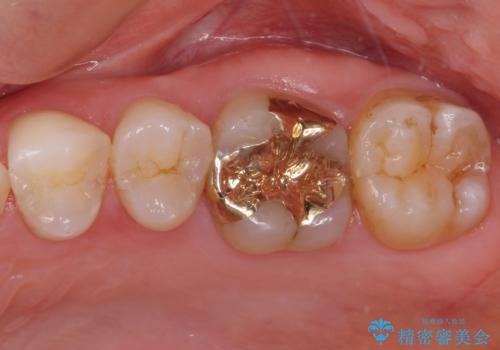

矯正治療後は、奥歯の虫歯や銀歯を補綴・修復治療することとしました。

PGA(ゴールド)クラウン、インレーの注意事項(リスク・副作用など)

- インレーおよびクラウンは脱離するリスクがあります

- 形成量はセラミックより少ないですが、歯の形成、修復後に歯に症状が出ることがあります

- 自費診療(保険適用外治療)となります